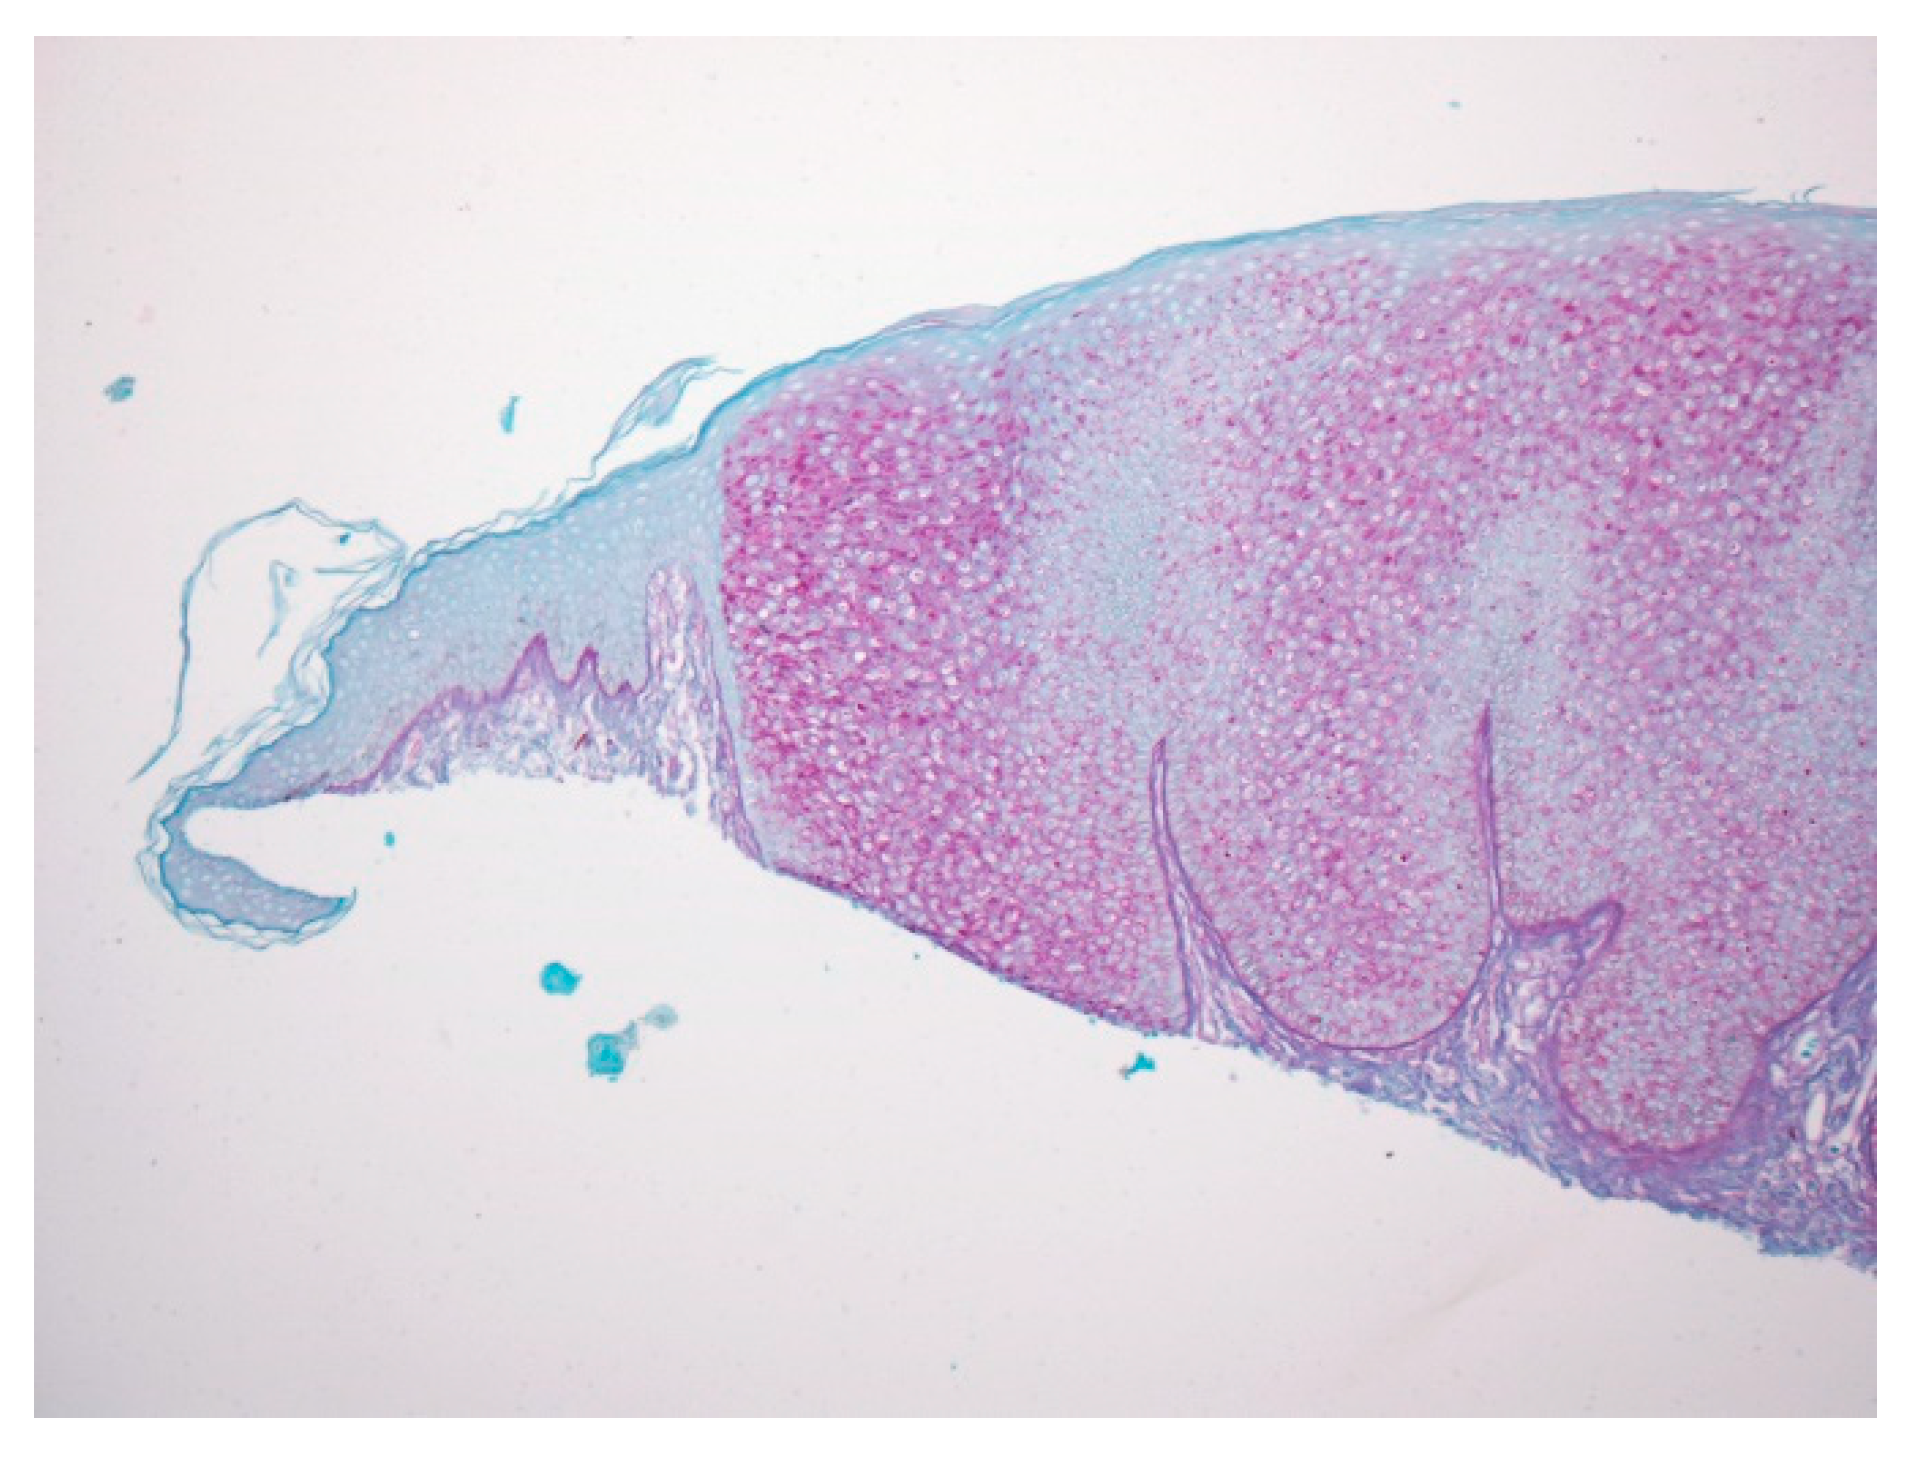

Figure 3.

With PAS staining, the lesion is sharply demarcated from the normal epidermis, suggesting glycogen accumulation in lesional keratinocytes.